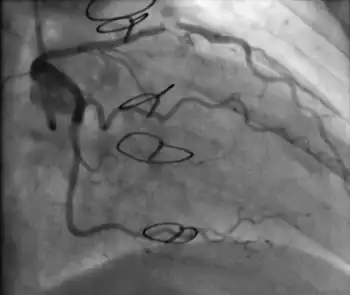

Coronary angiography

Surveillance is performed by regularly repeating coronary angiography in the cardiac catheterization laboratory, the diagnostic test of choice.[2] This is typically performed annually for the first five years after transplantation.[8] Angiography in CAV characteristically demonstrates diffuse stenoses in large coronary arteries and a reduced number of smaller coronary arteries, also known as "peripheral pruning".[2][6] However, because CAV frequently affects the entire length of the coronary artery, CAV may not be apparent by angiography alone.[2]

Partial occlusion of the left anterior descending artery on routine follow-up 8 months after transplantation.